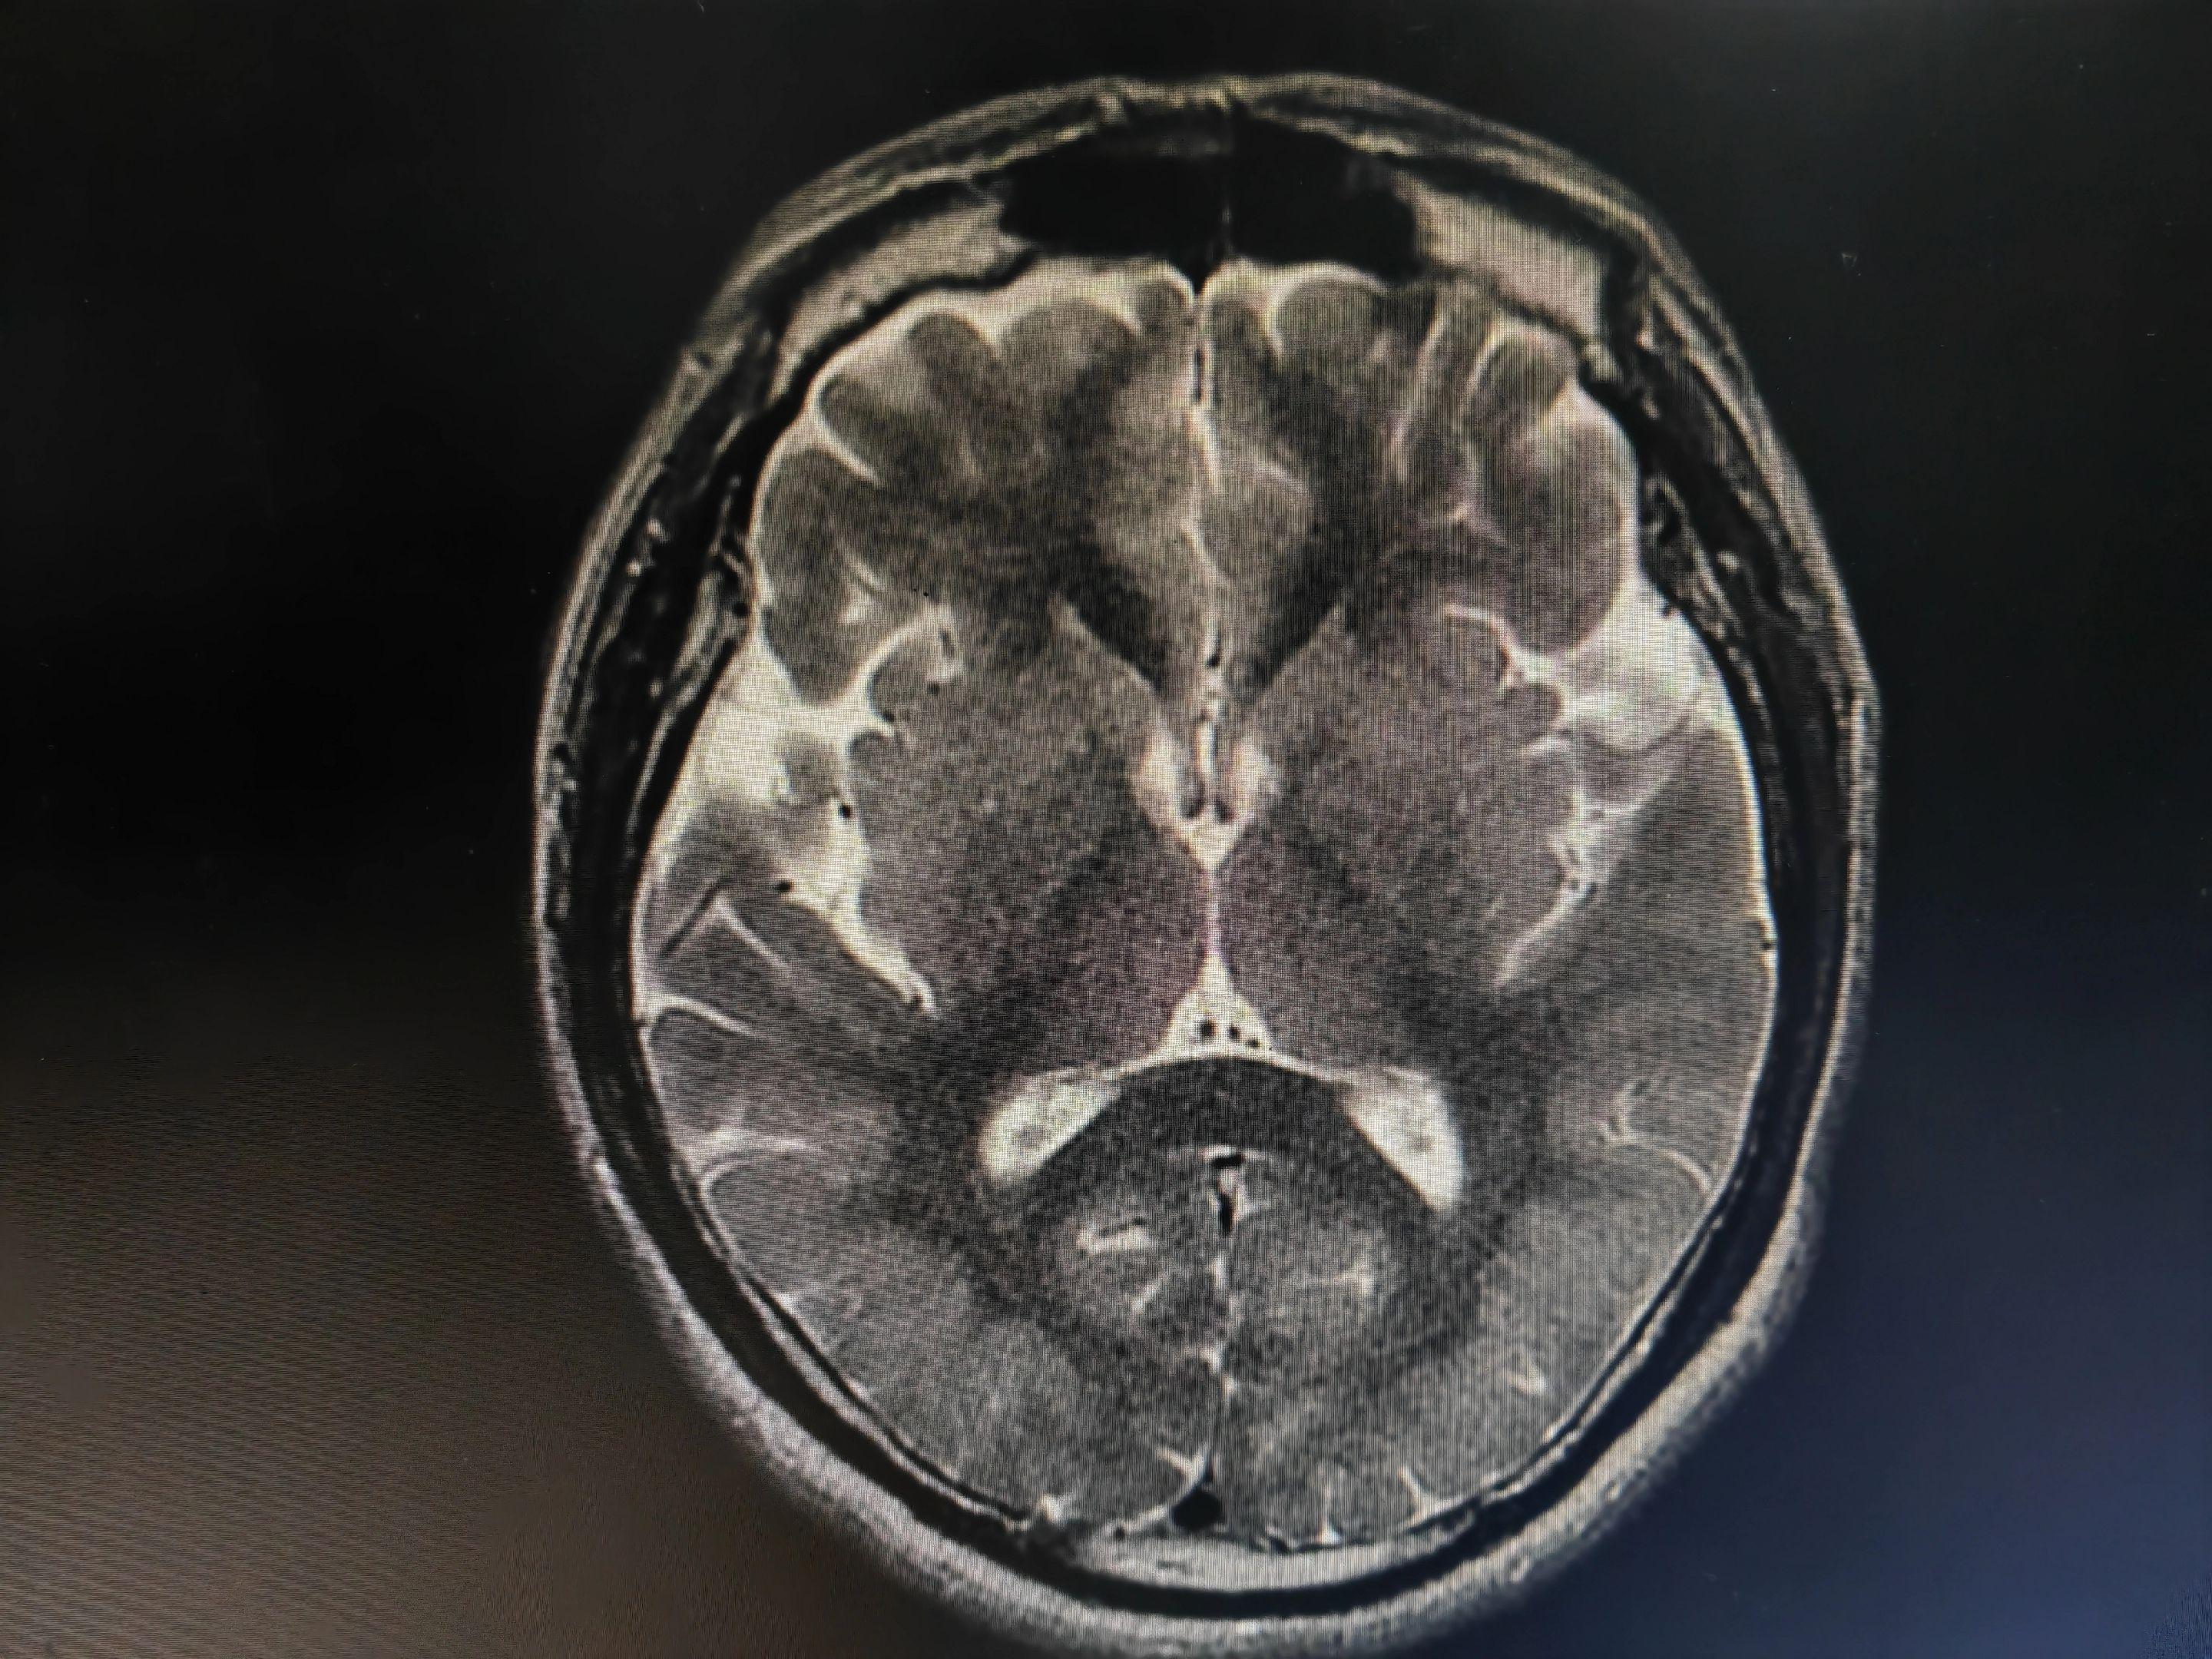

意识模糊伴言语不清的病人 中毒代谢性脑病几种最重要的影像学表现:白色即为受累区域,包括双侧对称性基底节和/或丘脑受累(图A),对称性齿状核受累(图B),皮层灰质受累(图C),对称性脑室周围白质受累(图D),皮质脊髓束受累(图E),胼胝体受累(图F),不对称性白质受累(脱髓鞘疾病;图G),枕顶枕部血管源水肿(图H),脑桥中央受累(I)。